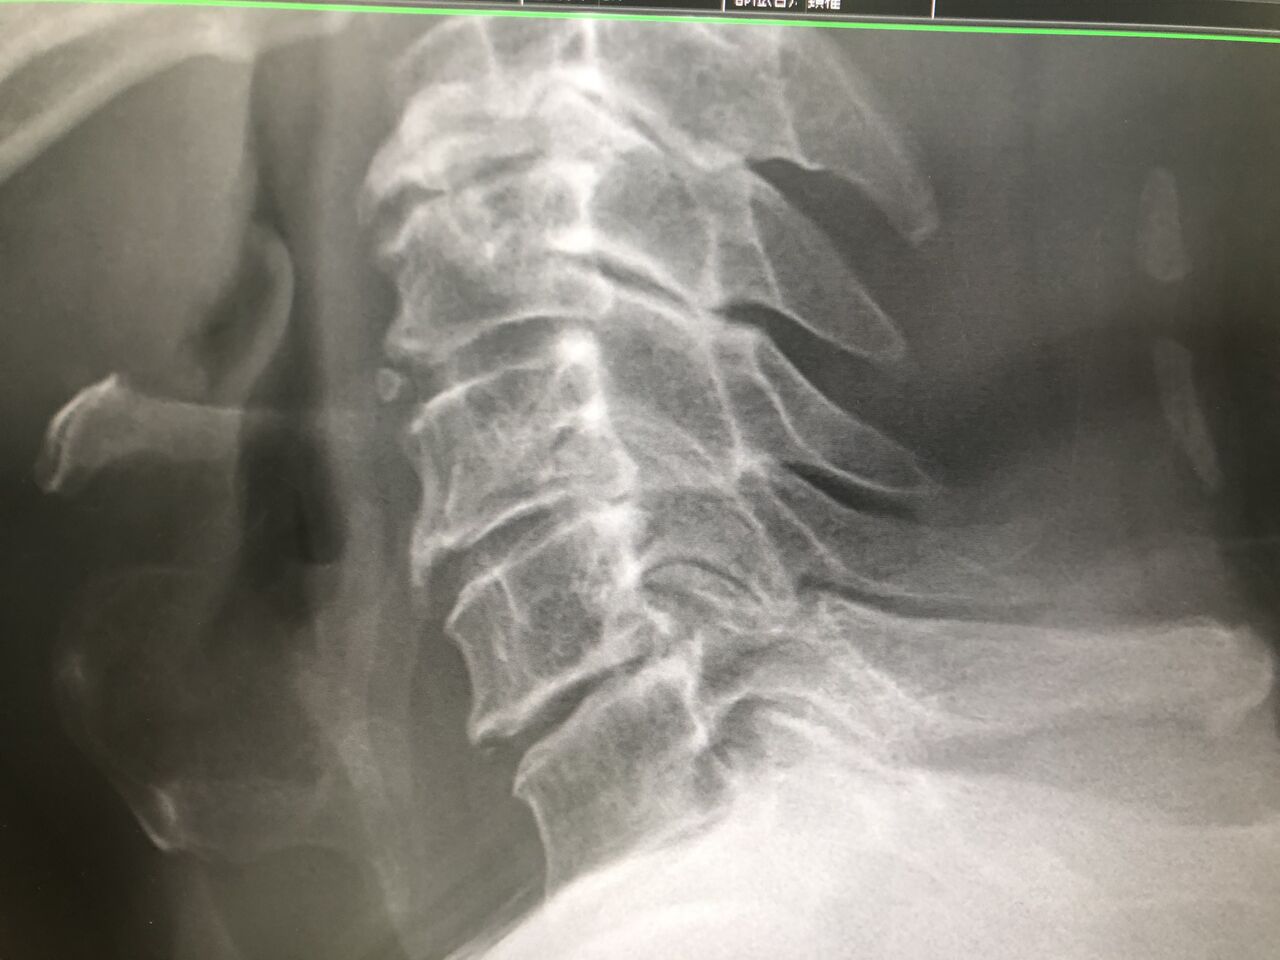

ゴルフ  シニア ティーチングプロ

本ツアープロです

変形が 出始めているので

筋トレ等を指導し、肩、首まわり、

筋肉を緩めて行きます